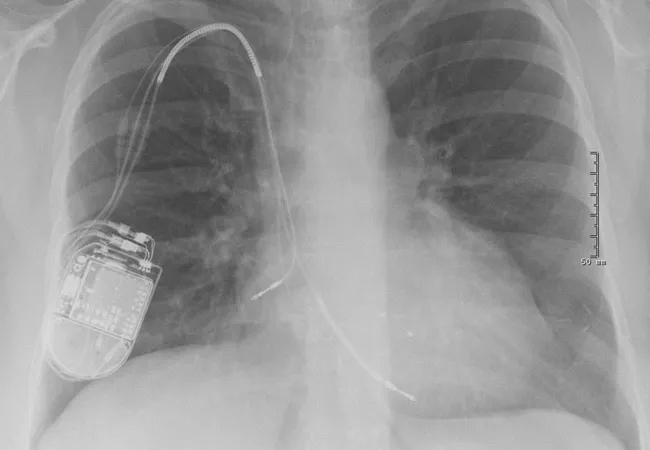

Preoperative chest X-ray (Figure 1) showed three leads. Because of her left-sided breast cancer and disrupted lymphatic system, the ICD device had been implanted on the right side.

Preoperative Chest X-Ray

Figure 1. Preoperative chest X-ray showing right atrial, right ventricular and coronary sinus leads.